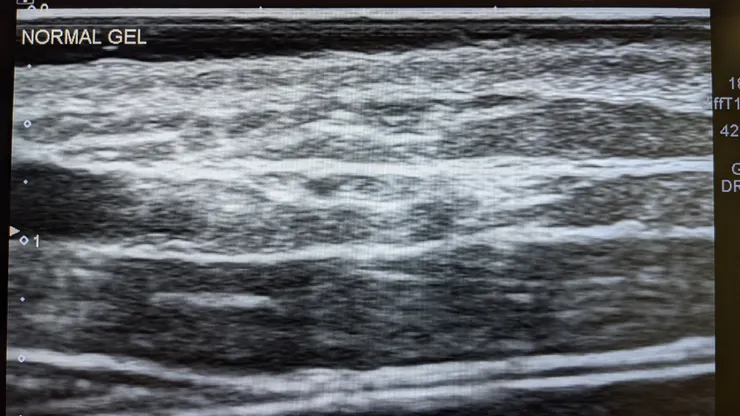

在超音波掃描時,音波沒有辦法通過空氣傳播。因此大多數的情況下沒有剃毛時毛髮與皮膚之間會有間隙存在。儘管超音波膠被設計出來的目的是為了更好的讓皮膚與探頭貼合,但毛髮與毛髮之間以及皮膚與毛髮之間的小空氣則沒有辦法很好的被超音波膠擠出,造成超音波下方的影像會出現假影遮蔽。

空口無憑,不如就來看看我們人為製造些小氣泡在傳導膠內會發生什麼事情吧!

掃描部位都選擇為成年智人的前臂、以線性探頭搭配日常在用的傳導膠以及均勻空氣混合的傳導膠進行掃描。

當然因為是實驗給予的氣泡量非常多很容易觀察。

日常掃描過程中氣泡數量多的時候當然會很容易地去區別,但一旦空氣數量沒那麼多的時候…

你真的分得出來嗎?